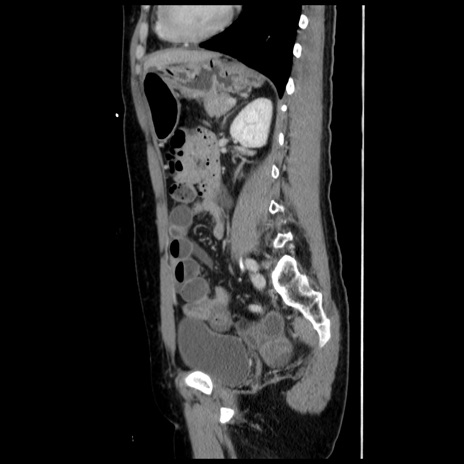

症例10(矢状断像)

【症例】 50歳代女性

【主訴】 腹痛

【現病歴】前日生レバーを食べた。今朝に排便あり。 昼前に突然発症の腹痛を生じ、当院救急外来を受診した。

【既往歴】 子宮筋腫にてで子宮全摘後

【身体所見】 意識清明、腹部:平坦、軟、下腹部やや左を中心に圧痛・反跳痛あり、筋性防御あり

【データ】WBC 7800、CRP 0.07